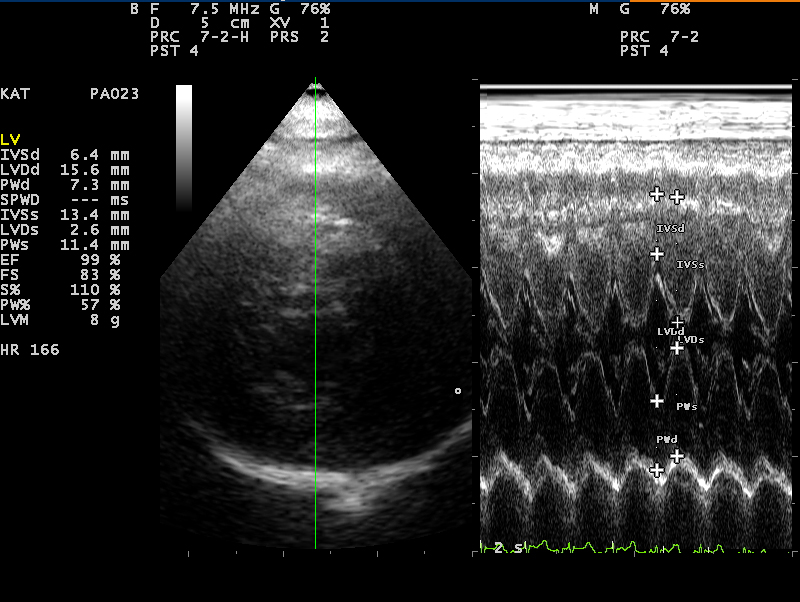

- Hart

85% van de katten met een hoge bloeddruk heeft ook een hartafwijking. De hartspier raakt verdikt door overbelasting waardoor een hartruis en/of een afwijkende hartritme op kan treden. Benauwdheid kan hiervan een vervelend gevolg zijn.